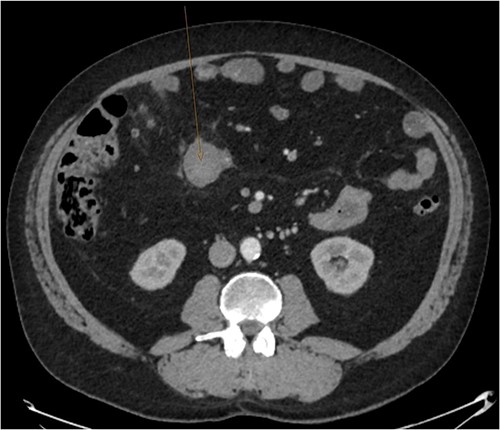

During admission the patient’s abdominal pain gradually improved, his Hb increased and he had no further coughing episodes. The patient was therefore stepped down to oral antibiotics and considered safe for discharge. A CT-AP four weeks post-discharge demonstrated a persisting 60 x 40 mm liquefying haematoma in the small bowel (Fig. 4), resolution of the peri-hepatic haematoma (Fig. 5) and interval reduction of the peri-splenic and pelvic haematomas. Given these improvements and the patient’s lack of significant symptoms, a plan to actively survey his progress was made.

Follow up CT angiogram showing improvement in mesenteric haematoma. Figure 4 is an axial section from the patient’s CT scan performed 4 weeks following discharge. The arrow highlights the patient’s liquefying mesenteric haematoma, which decreased from 104 x 62 mm to 60 x 40 mm. Combined with the improvement in the other areas of intra-abdominal bleeding and the patient’s overall clinical state, this image represents a significant improvement.

Follow up CT angiogram showing improvement in perihepatic haematoma. Figure 5 is another axial section from the patient’s CT angiogram performed 4 weeks following discharge and shows resolution of the perihepatic haematoma seen previously. Together with the other sections of the CT angiogram and the patient’s overall clinical state, the image represents a significant improvement in the patient’s intra-abdominal bleeding.